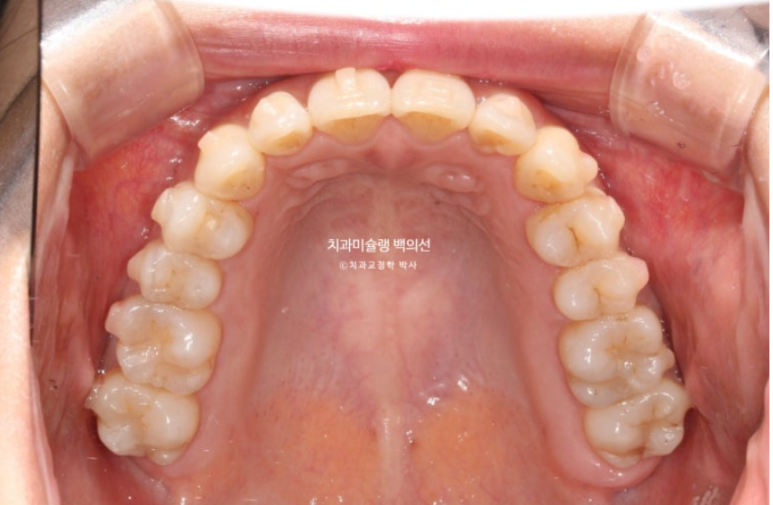

24년 8월부터 25년 4월까지, 31개 장치를 모두 낀 후 모습입니다.

31개 장치를 끼는 동안 중간 내원 횟수는 3회

환자분 협조도가 좋아서 나중엔 3달 간격으로 진료를 보았습니다.

25.04

중심선이 맞아지고 과개교합도 해결되었고 아래앞니 치축 기울어짐이 보입니다.

덧니가 배열되며 반대교합도 해소가 되었습니다.